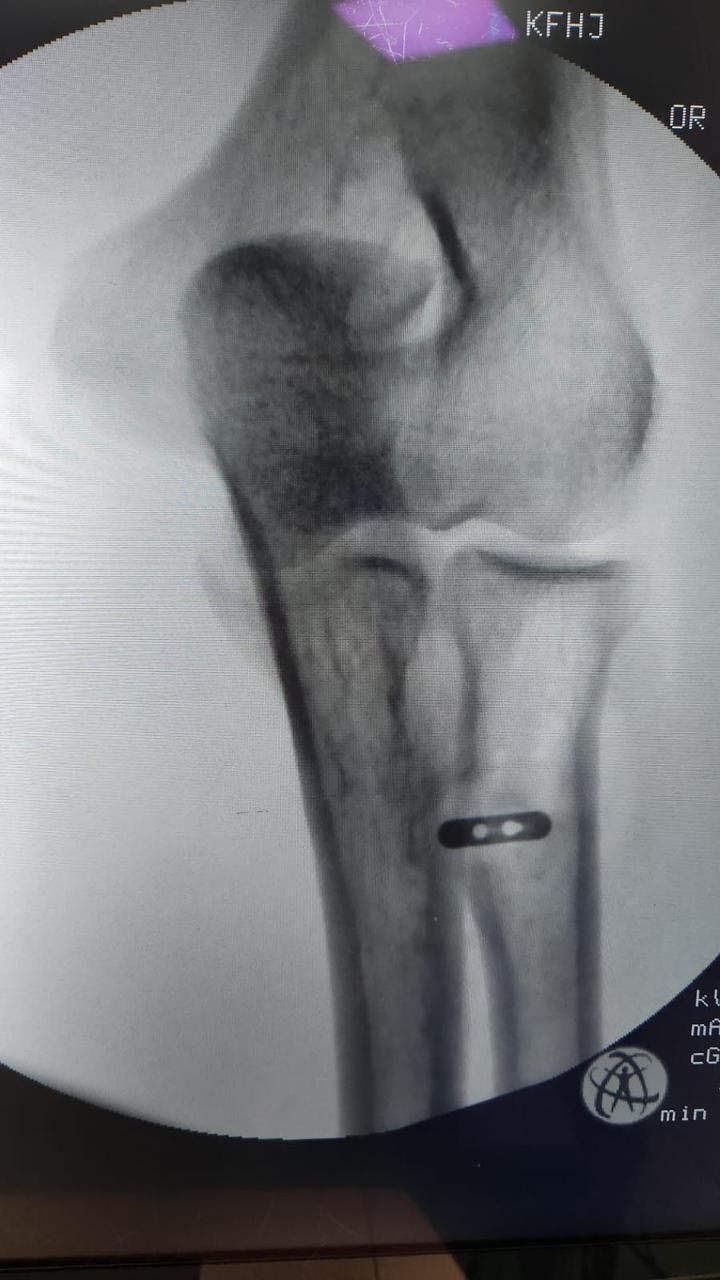

تمكن فريق طبي في جراحة العظام بمستشفى الملك فهد بجدة من إجراء عملية لمريض في الأربعين من عمره ، و إعادة وتره المقطوع ، نتيجة لتعرضه قبل شهر لقطع في العضلة التي تسمى البايسيبس ، و قد تمكن الفريق من إعادة و تثبيت الوتر المقطوع لمكانه بقيادة الدكتور شهاب بوسطجي استشاري الزمالة الألمانية في جراحة العظام و إصابة الملاعب بمستشفى الملك فهد بجدة .

و أشار الدكتور بوسطجي رئيس الفريق الطبي الذي أجرى العملية أنه قد تم إجراء الفحوصات اللازمة للمريض قبل العملية  من أشعة رنين مغناطيسي ، مضيفاً إلى أن هذا النوع من العمليات يُعد نادراً و من العمليات الدقيقة جداً التي تحتاج وقتاً للعودة لوضعها الطبيعي .